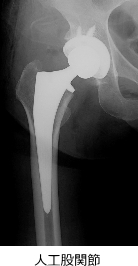

- 人工股関節置換術(THA):軟骨が消失した場合に適応。変形した関節を人工関節に置き換え、痛みを大きく軽減できます。

※近年は人工関節の耐用年数が向上しており、40〜50代でも適応となるケースがあります。

- 人工股関節置換術(広範囲の壊死に適応)